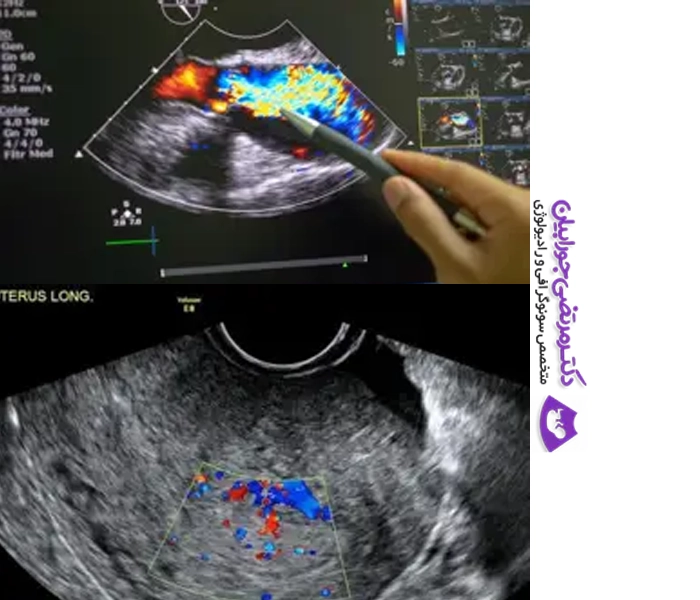

سونوگرافی رنگی (داپلر رنگی) یکی از روشهای پیشرفته تصویربرداری پزشکی است که جریان خون در عروق بدن را بهصورت رنگی و زنده نمایش میدهد. این روش کاربرد زیادی در ارزیابی سلامت عروق و تشخیص اختلالات جریان خون دارد و نسبت به سونوگرافی ساده اطلاعات دقیقتری ارائه میدهد.

امکان مشاهده جهت، شدت و سرعت جریان خون در شریانها و وریدها بهصورت دقیق. - تشخیص لخته یا انسداد عروق

کاربرد مهم در بررسی بیماریهای قلبی، نارساییهای عروقی و مشکلات دریچهای قلب. - کنترل گردش خون جنین و جفت در بارداری

برای بررسی سلامت جنین، تشخیص رشد داخلرحمی، یا بررسی خطر پرهاکلامپسی. - تشخیص تومورها و تودههای عروقی

با مشاهده الگوی خونرسانی غیرعادی میتوان ماهیت بدخیم یا خوشخیم بودن توده را بررسی کرد. - کمک به تشخیص و درمان واریس و ترومبوز وریدی (DVT)